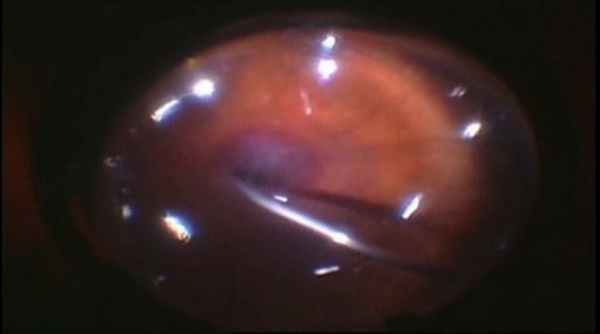

Клинический случай. Эндофтальмит после экстракапсулярной экстракции травматической катаракты.

Вид операцинонного поля.

Этапы операции.

Начало операции.

В ходе операции удаления изменённого стекловидного тела.

Удаление гнойного экссудата на периферии на заключительном этапе операции.

Заполнение витреальной полости силиконовым маслом в конце операции.